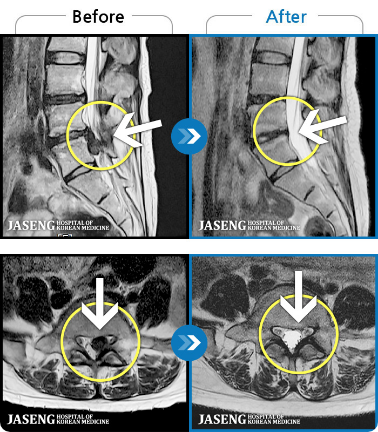

Before

After

하지 저림과 통증이 개선되어서 일상생활이 너무 즐겁습니다.

2024.08.12 ~ 2025.02.26

좌측 허리 통증으로 허리를 반듯이 펴고 서있기 힘들어 내원하셨습니다.

발병 전만큼 좋아져서 완치되었다는 마지막 진료를 받고 이번주 수요일 기분 좋게 병원을 퇴원 했습니다. 감사합니다.